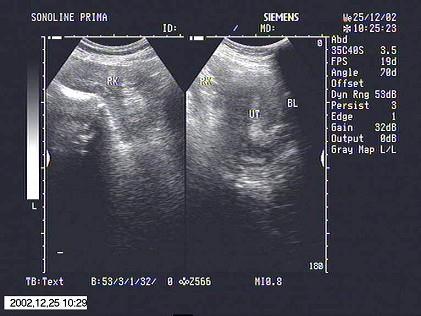

超声探查,子宫旁边有一类似肾脏的光团,最可能诊断为?(?)A.游走肾B.异位肾C.肾下垂D.融合肾E.盆腔占位

问题 超声探查,子宫旁边有一类似肾脏的光团,最可能诊断为?(?)

选项 A.游走肾 B.异位肾 C.肾下垂 D.融合肾 E.盆腔占位

答案 B